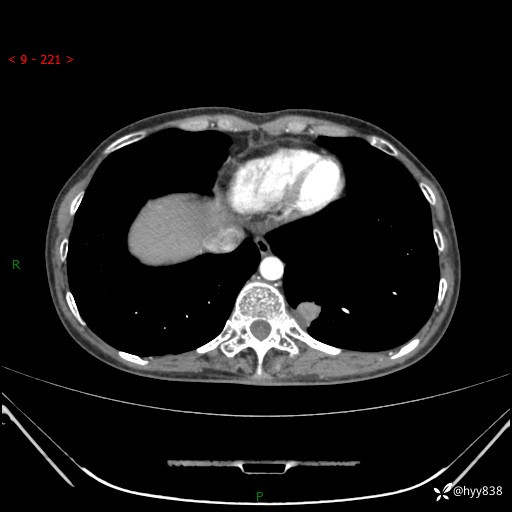

胸部CT平扫

增强动脉期+静脉期

各期CT值:48hu 65hu 76hu